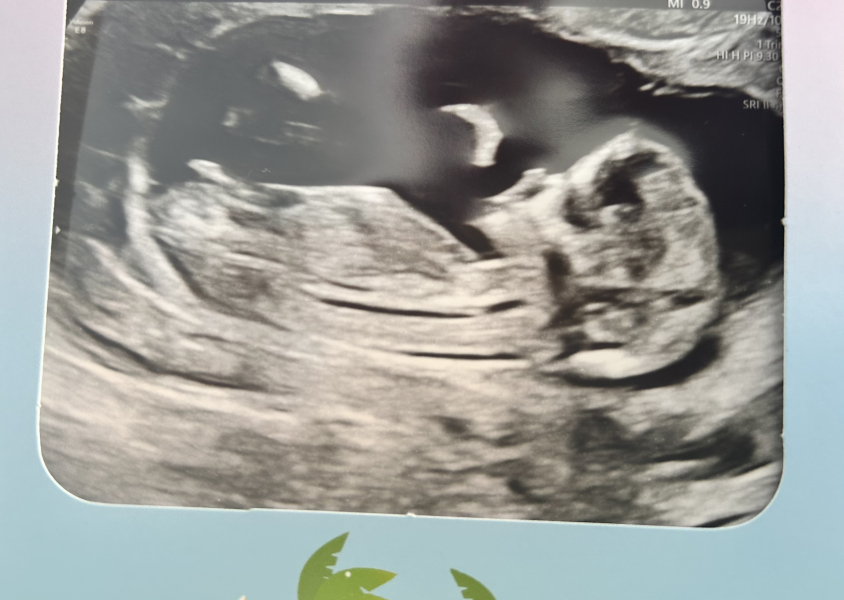

longingtobe23 · 15/03/2024 12:05

I was further along today! Chuffed 😅 13+2

due the same day as my nans birthday and I wanted to name the baby after her if it’s a girl!

But I have no idea how to guess gender I am not bothered either way! Just so so happy it’s done and went well!!

they messed up my bloods again - also butchered me trying to get them out (I have crap veins) but I had treat after now on the sofa trying to relax 😂

Best of luck all for today!